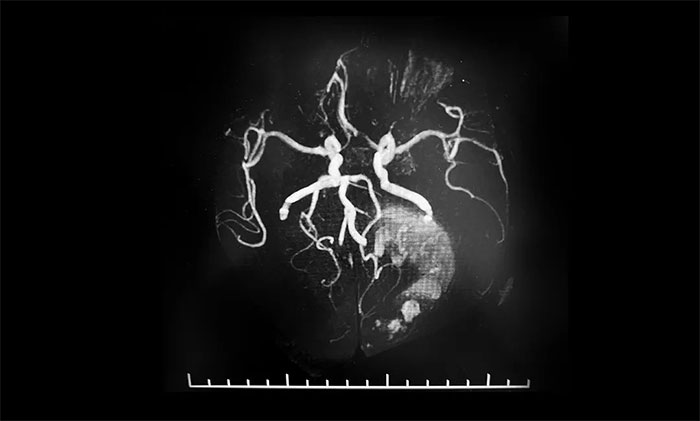

▲ 術(shù)前MRA,了解腫瘤供血情況

術(shù)前,潘仁龍主任給予患者脫水劑、白蛋白、甘露醇等藥物治療,患者病情逐漸穩(wěn)定,可以睜眼,身體相關(guān)指標(biāo)達(dá)到手術(shù)條件。為了進一步降低手術(shù)風(fēng)險,李士其教授等專家團隊進行了詳細(xì)的術(shù)前準(zhǔn)備,包括手術(shù)設(shè)計、切口大小設(shè)計、手術(shù)備血等。同時,術(shù)前進行了磁共振血管成像,詳細(xì)了解腫瘤供血情況,確保手術(shù)可控,萬無一失。